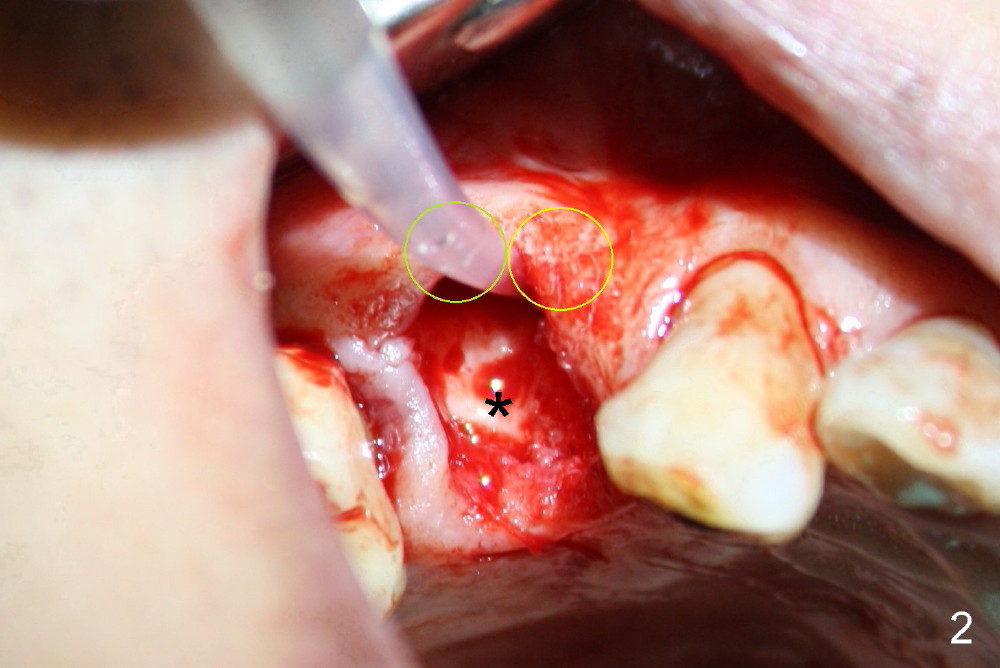

When the tooth is extracted, the two sockets (Fig.2 yellow circles, where the irrigation syringe is) are found to be buccally located, creating cantilever effect and probably leading to restoration failure/root fracture. There is bone palatal to the sockets (*). Bicon reamers are used to form osteotomy and collect autogenous bone at the same time (because of 50 RPM). A 5x17mm implant is placed, in alignment with arch form (Fig.3 blue curved line). The future restoration will be along the long axis of occlusion. Therefore the immediate implant achieves "instant orthodontic result".

Buccal flap is raised (Fig.4) for bone graft and collagen membrane. The graft is autogenous, harvested using the reamers mentioned above and mixed with Bicon Synthograft.